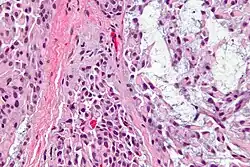

Normal histology of the breast, with myoepithelial cell annotated near bottom right.

Myoepithelial cells (sometimes referred to as myoepithelium) are cells usually found in glandular epithelium as a thin layer above the basement membrane but generally beneath the luminal cells. These may be positive for alpha smooth muscle actin and can contract and expel the secretions of exocrine glands. They are found in the sweat glands, mammary glands, lacrimal glands, and salivary glands. Myoepithelial cells in these cases constitute the basal cell layer of an epithelium that harbors the epithelial progenitor. In the case of wound healing, myoepithelial cells reactively proliferate. Presence of myoepithelial cells in a hyperplastic tissue proves the benignity of the gland and, when absent, indicates cancer. Only rare cancers like adenoid cystic carcinomas contains myoepithelial cells as one of the malignant components.

Myoepithelial cells are true epithelial cells positive for keratins, not to be confused with myofibroblasts which are true mesenchymal cells positive for vimentin. These cells are generally positive for alpha smooth muscle actin (αSMA), cytokeratin 5/6 and other high molecular weight cytokeratins, p63 and caldesmon. Myoepithelial cells are stellate in shape and are also known as basket cells. They lie between the basement membrane and glandular epithelium. Each cell consists of a cell body from which 4-8 processes radiate and embrace the secretory unit. Myoepithelial cells have contractile functions. They help in expelling secretions from the lumen of secretory units and facilitate the movement of saliva in salivary ducts.